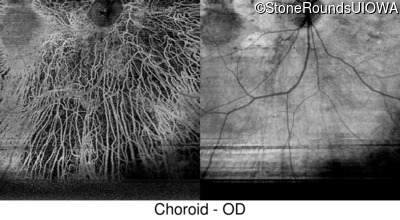

Swept-Source OCT - Right - 20/20 +1

Exemplar